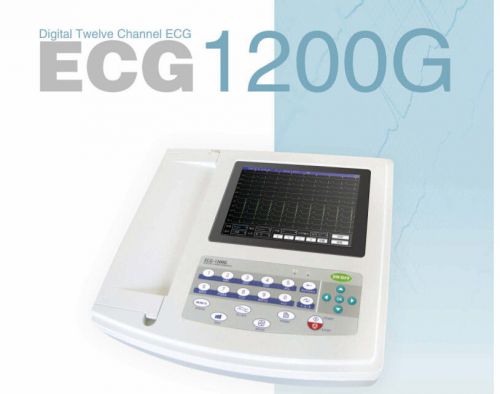

CE,CONTEC Digital 12 Channel ECG1200G Color LCD 12-LEAD ECG,USB+ Free Software